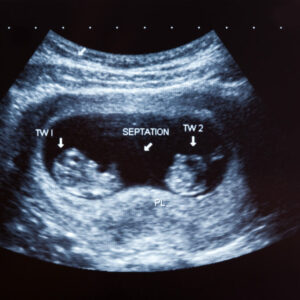

Técnica enfocada a lograr la unión del óvulo con el espermatozoide en el laboratorio